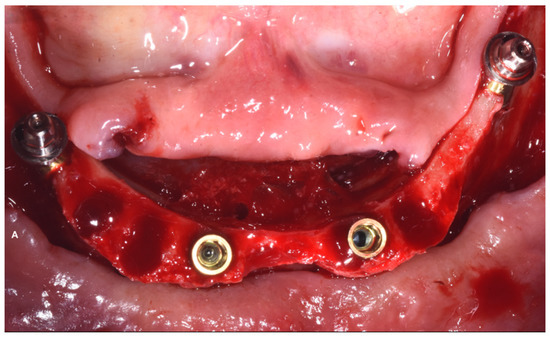

2. Case Report

Surgery Appointment